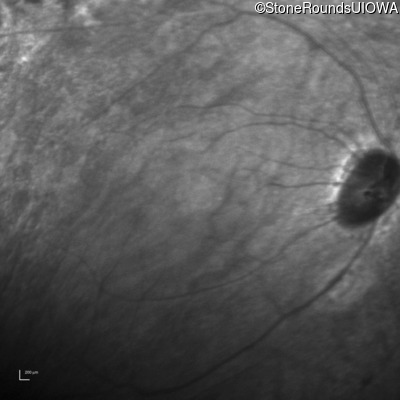

Infrared Fundus Photograph - Right - 20/70 -2

Exemplar